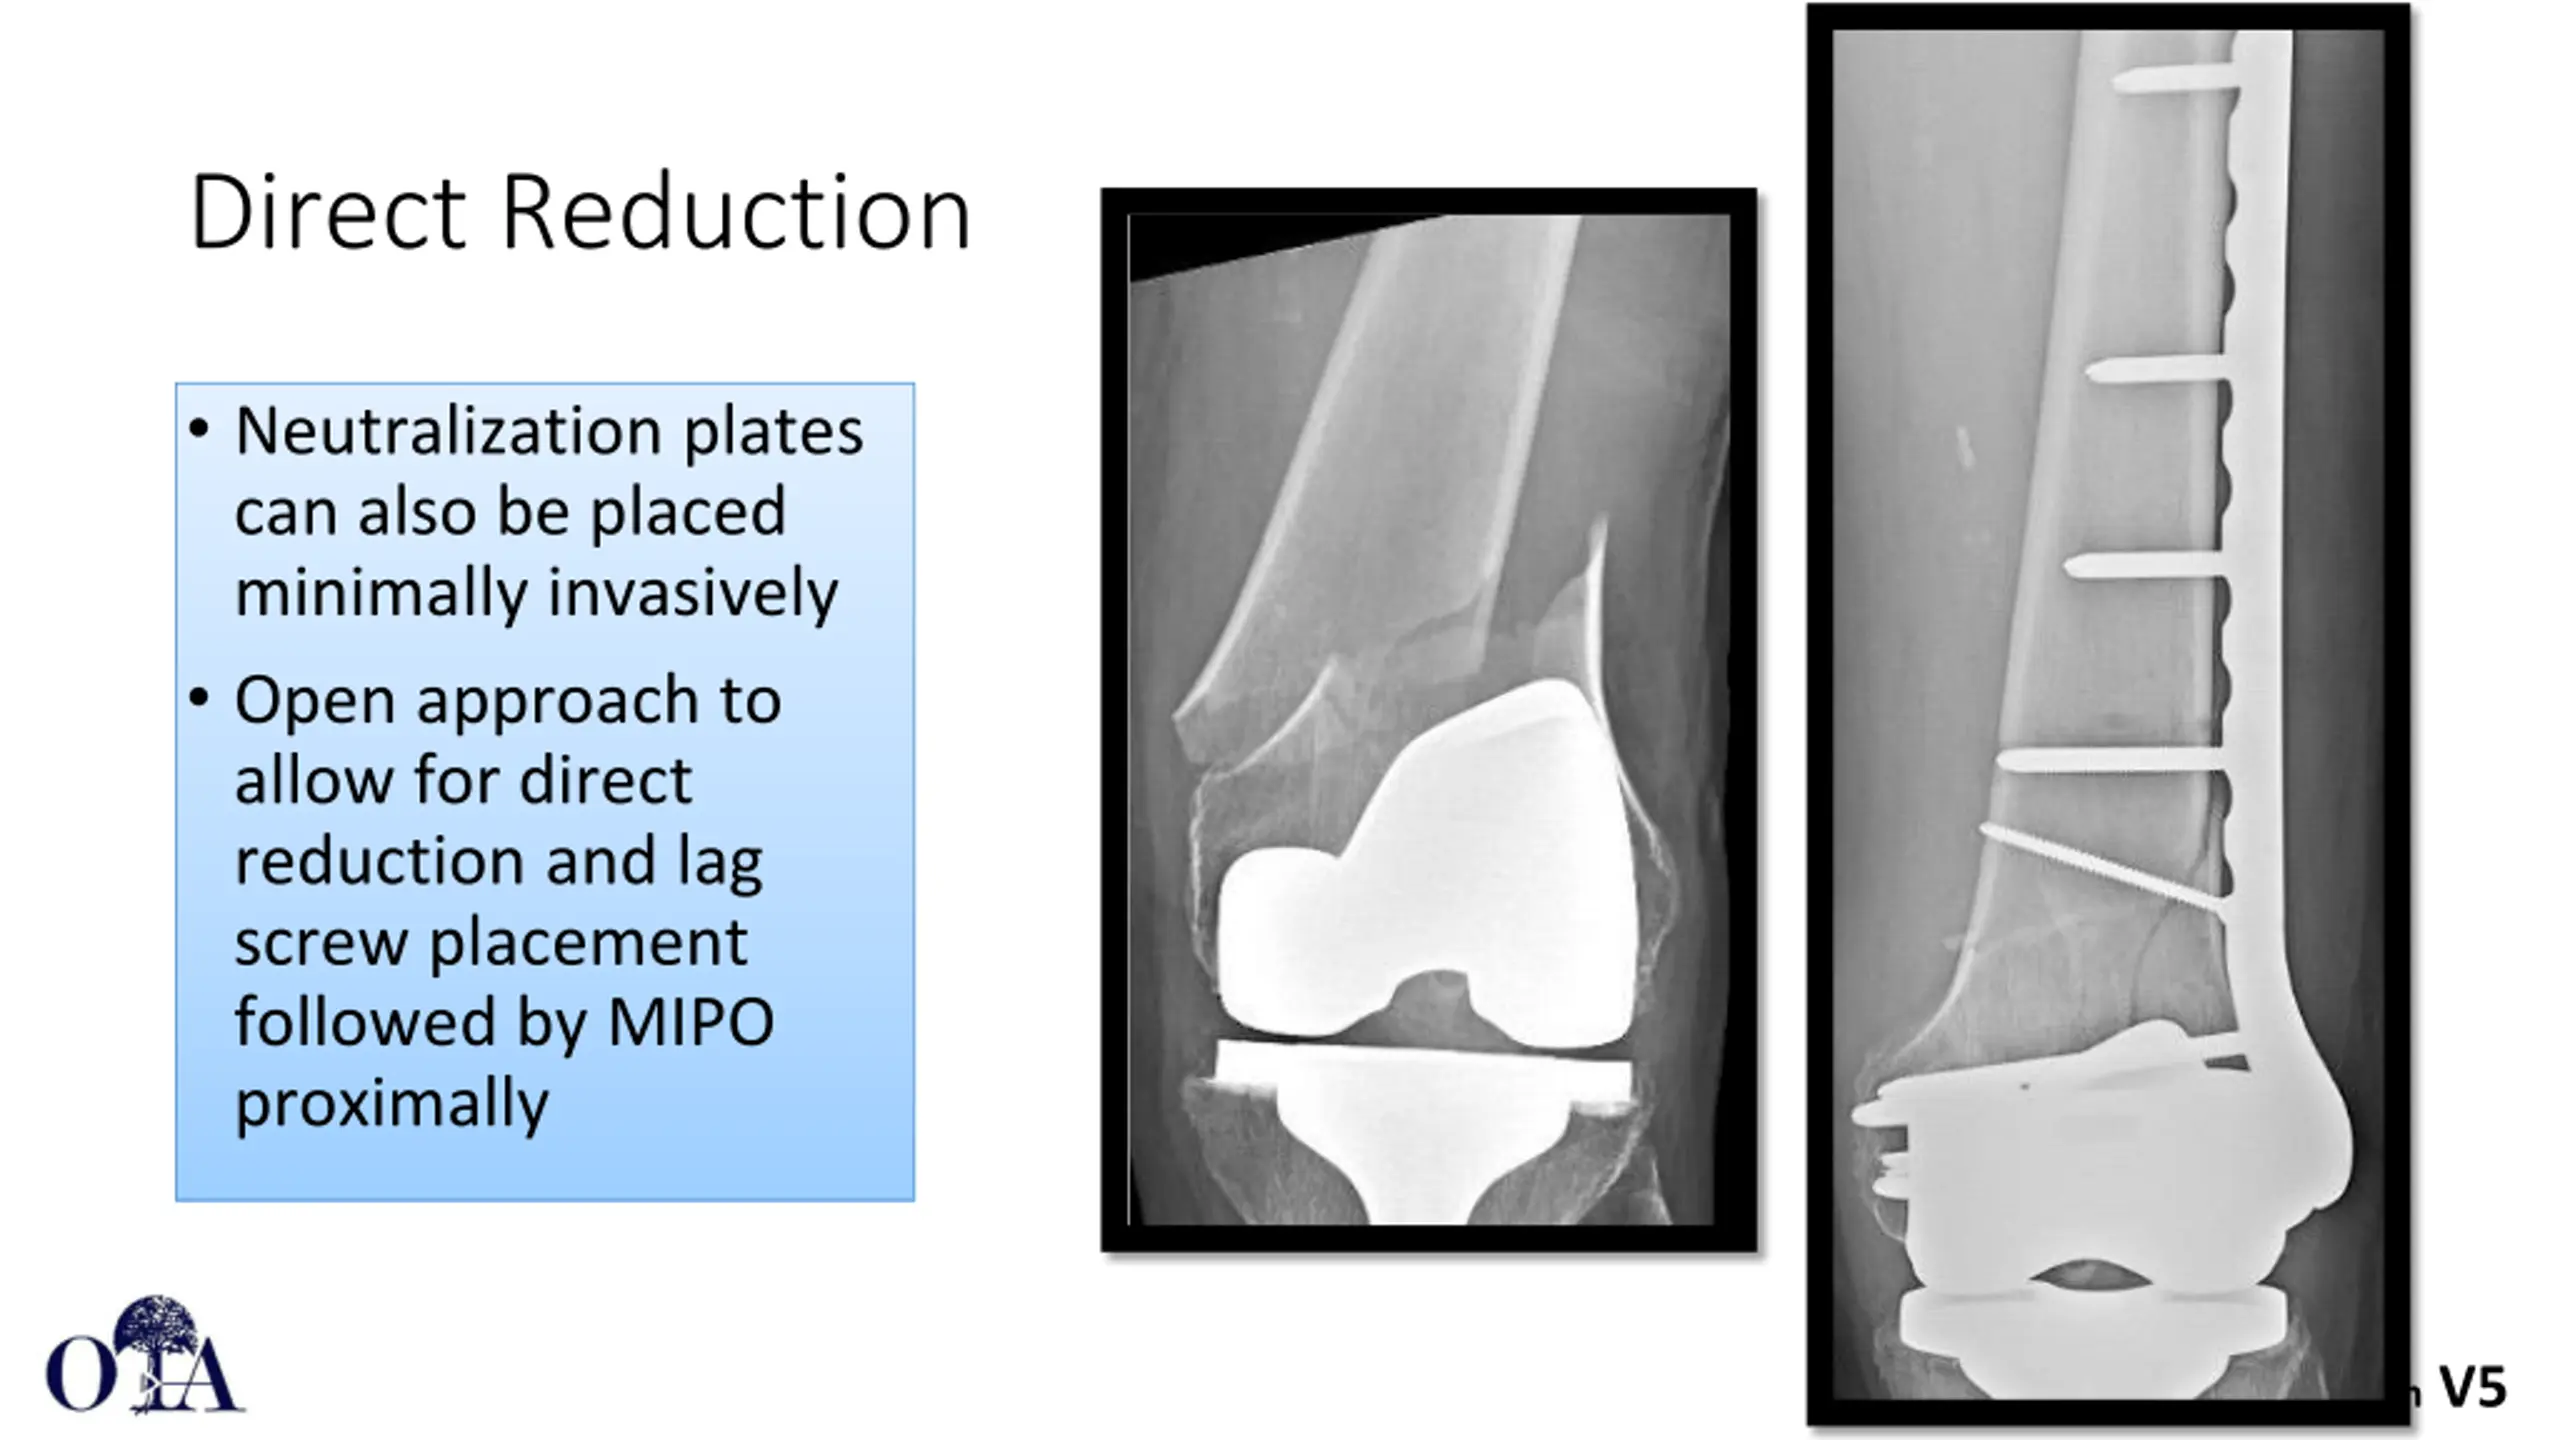

Direct Reduction Neutralization plates can also be placed minimally invasively Open approach to allow for direct reduction and lag screw placement followed by MIPO proximally Core Curriculum V5